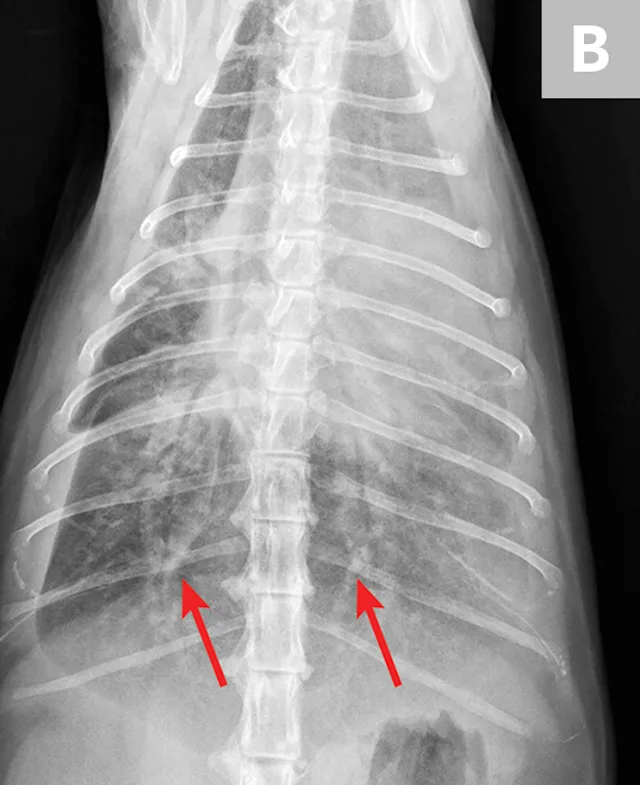

FIGURE 4

Radiograph of pulmonary abscessation. The pulmonary nodules (arrows) could be mistaken for pulmonary neoplasia. The margins of these nodules are slightly less well demarcated than in neoplasia. Improvement was achieved with antibiotic therapy.